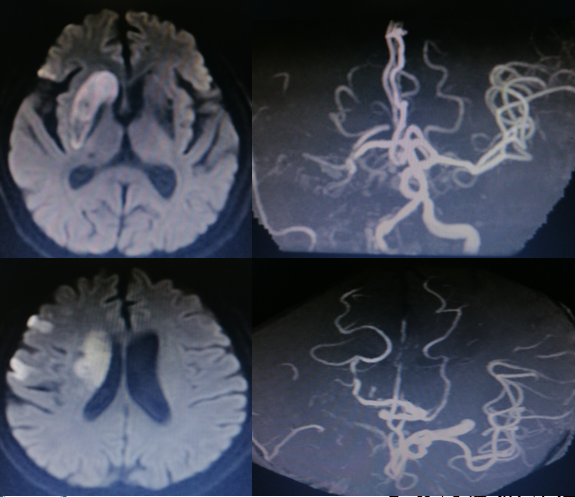

影像诊断

病历夹什么径技·第151期|串联营病历夹:京广连营_https://www.jmylbn.com_新闻资讯_第72张

病历夹什么径技·第151期|串联营病历夹:京广连营_https://www.jmylbn.com_新闻资讯_第73张

病历夹什么径技·第151期|串联营病历夹:京广连营_https://www.jmylbn.com_新闻资讯_第74张

<<滑动查看下一张图片>>

结论:颅脑CT提示左侧基底节、放射冠区腔隙样软化灶。颅脑DWI提示双侧小脑、桥脑、中脑、双侧海马、双侧枕叶、右侧丘脑及右侧胼胝体多发急性脑梗塞。颅脑MRA提示基底动脉及双侧大脑后动脉未见显示;右侧大脑中动脉中-重度狭窄;脑动脉硬化。初步诊断为急性后循环脑梗死,基底动脉闭塞。

• 左侧椎动脉造影见基底动脉起始处闭塞。

• 微导管造影,见基底动脉尖及左侧大脑后动脉显影不良,考虑栓塞。

• 基底动脉近端打开支架,支架形态尚可,局部发白,左侧大脑前动脉P1段栓塞。

• 支架取栓取出一小块栓子,造影见基底动脉起始处重度狭窄。

• 狭窄处予球囊扩张成形,球扩后造影见基底动脉狭窄有所改善。

• 微导管送至左侧大脑后动脉P2段,造影确认真腔后,释放支架,并支架取栓1次。

• 血栓成功取出,基底动脉侧位造影,左侧大脑后动脉再通。

• 正位造影,左侧大脑后动脉再通,无血栓逃逸,基底动脉狭窄改善,未回缩,前向血流正常,观察后结束手术。

病历夹什么径技·第151期|串联营病历夹:京广连营_https://www.jmylbn.com_新闻资讯_第78张

病历夹什么径技·第151期|串联营病历夹:京广连营_https://www.jmylbn.com_新闻资讯_第79张

病历夹什么径技·第151期|串联营病历夹:京广连营_https://www.jmylbn.com_新闻资讯_第80张

• 患者术后转入重症医学科,症状一直未有改善,昏迷状,术后第5天家属放弃治疗自动出院。